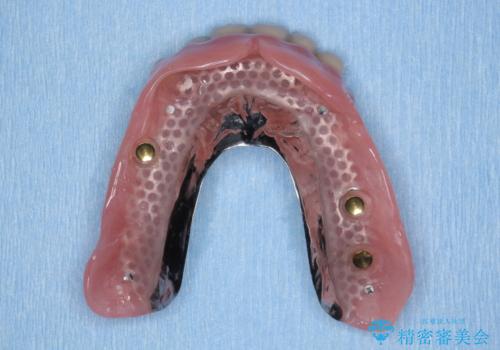

インプラント支台のマグネットを用いることで安定してしっかりと噛めるような総義歯治療を計画します。

- 100万円(インプラント・マグネットアバットメント×3・金属床義歯)費用は治療当時の料金となります

通常の入れ歯は歯ぐきで支えるため話したり食事の際に動いたり安定が悪くなってしまうことが多いですが、インプラント支台のマグネットを設定することでより安定してしっかりと噛むことができるようになります。